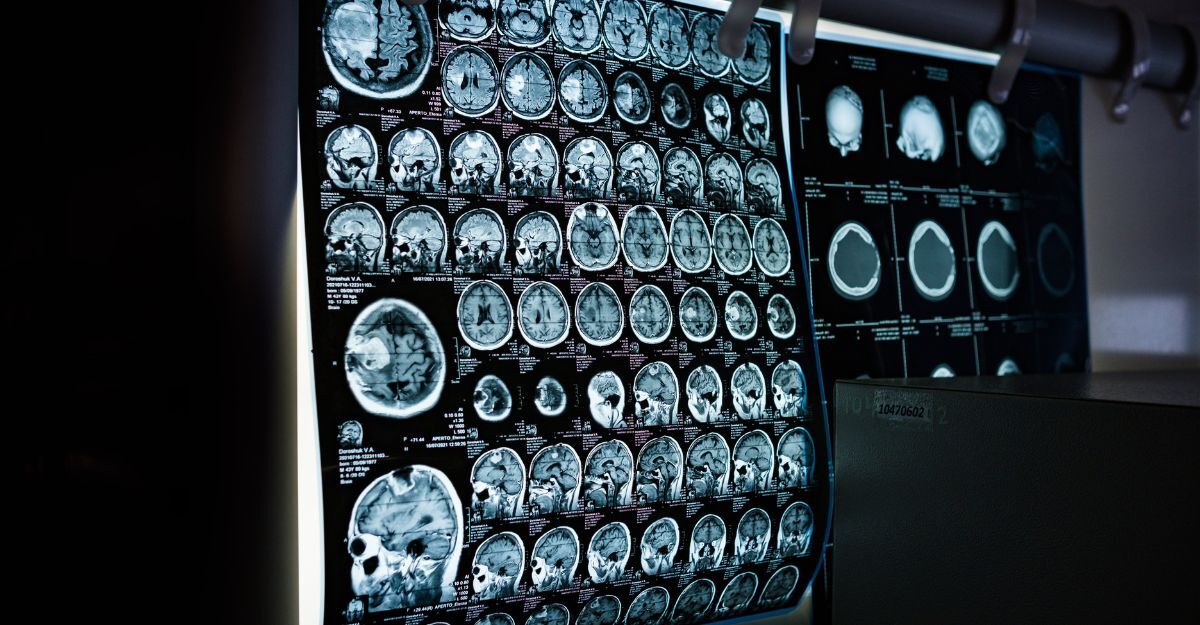

Le molecole in questione, lecanemab e donanemab, sono anticorpi monoclonali progettati per agire direttamente sulle placche di beta-amiloide nel cervello, con l’obiettivo di modificare il corso della malattia, piuttosto che limitarsi a gestirne i sintomi.

Gli studi clinici condotti hanno dimostrato che, in pazienti trattati nelle fasi iniziali, i farmaci possono rallentare il deterioramento cognitivo e funzionale.